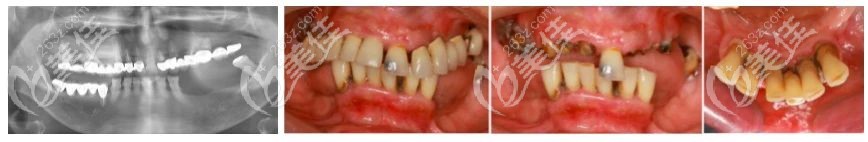

術(shù)前照片:

術(shù)前無(wú)牙頜老人口腔情況

口內(nèi)有多個(gè)不良修復(fù)體且余留牙均有松動(dòng),下頜后牙區(qū)的垂直向骨量吸收嚴(yán)峻,牙齒不整齊。